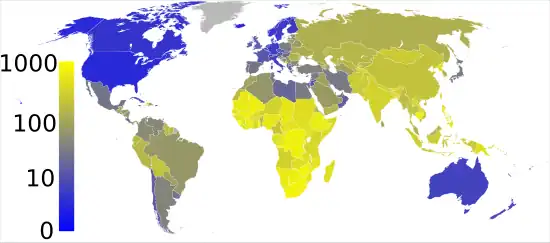

En 2023, après la pandémie de Covid-19, elle arrive en seconde place des causes de mortalité d'origine infectieuse à l’échelle mondiale, devant le sida[1]. L'Organisation mondiale de la santé (OMS) rapporte à travers son rapport annuel consacré à la tuberculose et sorti en 2015 que 1,5 million de personnes sont mortes de la tuberculose l’année précédente[2]. Parmi les nouveaux cas de tuberculose enregistrés en 2019, 87 % sont survenus dans les trente pays présentant la plus forte charge de la maladie. Deux tiers des cas sont concentrés dans huit pays, avec l’Inde en tête, suivie de l’Indonésie, de la Chine, des Philippines, du Pakistan, du Nigéria, du Bangladesh et de l’Afrique du Sud[3].

Le nombre annuel de nouveaux cas dans le monde, incluant les cas de rechute, était en 2006 d'environ 5,4 millions[29]. Il était en 2018 estimé à dix millions par l'OMS[30]. Environ 58 % des nouveaux cas se trouvent dans la région sud-est de l’Asie et les régions du Pacifique ouest. L'OMS estime par ailleurs qu'environ un quart de la population mondiale est porteuse d’une tuberculose latente, c’est-à-dire est porteuse de la bactérie sans toutefois développer de symptômes et sans être contagieuse. L'organisme estime entre 5 et 15 % le risque pour les porteurs sains de développer la maladie à un moment de leur existence[30].

La prévalence de la tuberculose en 2015 a chuté de 42 % depuis 1990. Elle varie d'un pays à un autre en fonction de plusieurs facteurs dont le niveau socio-économique ; le rapport annuel de l'OMS nous apprend que les pays en développement sont les plus touchés (95 % des cas) et en particulier la région de l’Asie du Sud-Est, avec 44 % des nouveaux cas et l'Afrique (28 % des nouveaux cas mondiaux en 2018). La tuberculose est une cause majeure de mortalité chez les personnes infectées par le VIH. Elle serait responsable de 13 % environ des décès par sida dans le monde[31].

Environ 1,5 million de personnes sont mortes de la tuberculose en 2018, dont une personne sur six était porteuse du VIH.

La tuberculose, sans bénéficier de programmes de prévention et de cure aussi importants, tue ainsi à peu près deux fois plus[32] que le sida, soit environ 4 000 personnes par jour[33].

- Le fait de vivre en Asie est un facteur prédisposant : la plupart des nouveaux cas (49 %) se situent dans les zones peuplées d'Asie : Bangladesh, Pakistan, Inde, Chine et Indonésie. Il existe une augmentation dans les pays de l'Europe de l'Est dont la Russie[45] et l'Ukraine[46]. La croissance reste très forte en Afrique, avec près de 13 % contre moins de 1 % dans les pays asiatiques.